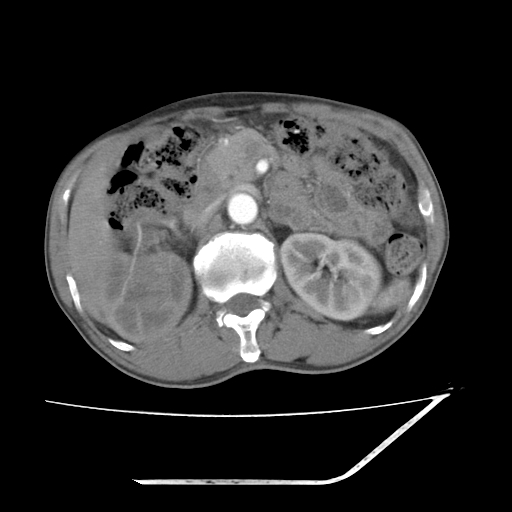

增强

考虑右肾盂癌,肾动脉受侵,右肾功能减退,右肾盂输尿管积水,管壁增厚,考虑种植转移,应该把下面扫完的

考虑右侧肾盂癌。右侧输尿管扩张未扫描完。

右肾盂癌,肾动脉受侵,右肾盂输尿管积水,管壁增厚,考虑种植转移

右肾盂移行细胞癌并右输尿管中段转移.肾积水.

1.右侧肾盂癌伴肾盂积水。

2.肾脏功能减退,原因有:(1)肾动脉受侵。(2)肾静脉受侵(3)肾积水,等。本例,肾动脉显影较好,但受压明显;肾静脉无明显显示,受压或静脉癌栓,下腔静脉腔内未见明显充盈缺损。

3.右侧上段输尿管扩张,原因:(1)积水所致;(2)种植。